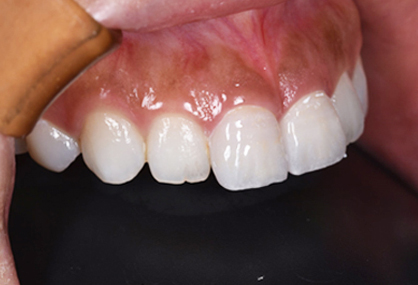

仮歯

セラミックの前に仮歯を調整している段階になります。できればということで歯の長さも短くしたいというリクエストがありましたので、仮歯で調整をしながら様子を見ました。

歯の長さを短くする際に歯を削りますので神経の治療が必要になることがありますので、しみたり・噛んで痛くないか?を約1ヶ月様子を見ました。色・形など仮歯でほぼ問題ないということでしたので、最終的な型採りをしました。